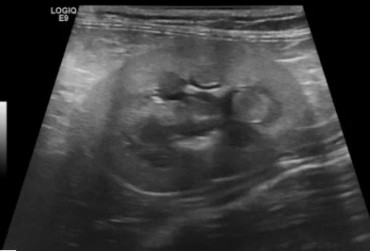

Kot syberyjski, samiec, 4l. Robaczyca jelit cienkich.

24 czerwca 2019

Wojciech Atamaniuk

Czytaj więcej